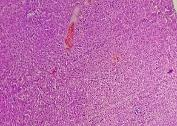

All the animals were observed daily for clinical signs of toxicity and morbidity. Individual animal body weights were recorded at receipt (on day 1) and weekly thereafter and at the time of sacrifice (fasting body weights). Histological examinations of various organs (brain, kidney, liver, small intestine and stomach) were carried out after 28 d using haematoxylin and eosin as staining agents. The organs were preserved in 10 % formalin solution.

On administration of TPSY, the animals in all groups were found to survive at the end of 28 d of study. The histological results are shown in table 4. Liver tissue showed minimal degeneration of hepatocytes compared to control at the highest dose of 350 mg which was however reported to be non-toxic.

Mild tubular degeneration was observed in kidneys Stomach tissue displayed moderate changes compared to control, with minimal degeneration of mucosal cellsat highest dose of 350 mg. Large intestine showed marked submucosal edema but the mucosal tissue appeared to be normal at the highest dose of 350 mg. No abnormality was observed in brain tissues at a low and medium dose. Mild submucosal edema was observed at 350 mg/kg. These results point to the negligible toxicity associated with the thiolated polymer and hence it can be considered to be safe for use as a pharmaceutical excipient.

Table 4: Histological results of repeated dose toxicity studies of TPSY (n=5)

| Organs | Normal saline | TPSY dose strength | ||

| Control | 70 mg/kg | 175 mg/kg | 350 mg/kg | |

| Liver | Normal architecture of liver, nothing abnormal detected. | Nothing abnormal detected. | Minimal degeneration of hepatocytes. | Minimal degeneration of hepatocyte and infiltration of inflammatory cells. |

| Kidney | Normal architecture of kidney, nothing abnormal detected. | Minimal tubular degeneration. | Mild tubular degeneration and congestion of blood vessels. | Mild tubular degeneration. |

| Stomach | Normal architecture of Stomach, Nothing abnormal detected. | Minimal degeneration of mucosal lining cells. | Mucosal cells were enlarged and were darkly stained. | Minimal degeneration of mucosal cells, accumulation of dark staining material in the gland. |

| Brain | Normal architecture of the brain, Nothing abnormal detected. | Nothing abnormal detected. | Nothing abnormal detected. | Minimal neuronal degeneration. |

| Large intestine | Papillary projections with goblet cells. | Mucosal lining no infiltration of inflammatory cells. | Minimal infiltration of inflammatory cells and congestion. | Marked submucosal edema, mucosal tissue appears normal. |

![]() |

| A: Liver (Control) | B: Liver (350 mg/kg dose) |

| C: Kidney (Control) | D: Kidney (350 mg/kg dose) |

| E: Stomach (Control) | F: Stomach (350 mg/kg dose) |

| G: Brain (Control) | H: Brain (350 mg/kg dose) |

| I: Large Intestine (Control) | J: Large Intestine (350 mg/kg dose) |

Fig. 8: Histology of various tissues at highest dose strength of 350 mg/kg body weight